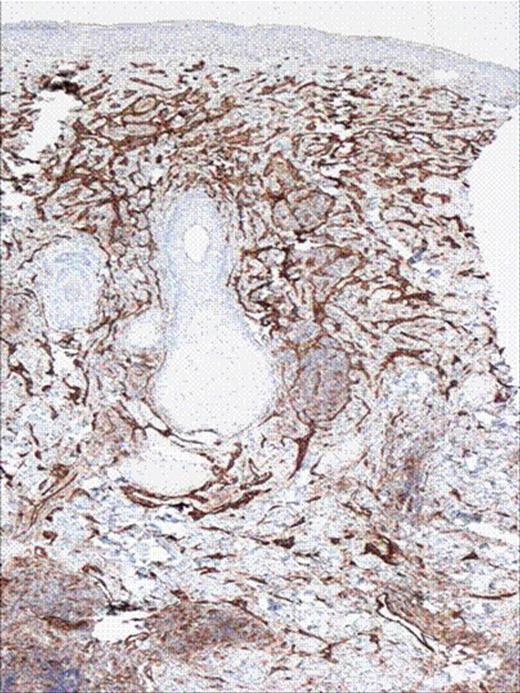

After 38 days of plasmapharesis platelet count stayed in the range of 10–20 and pericardial effusion was stable. We decided to consider the alternative diagnosis of acute on chronic DIC. Patient was started on Fondaparinux at a dose of 2.5mg initially for 3 days and then increased to 5mg SQ. On day 7 of Fondaparinux the platelet count was 137 from 20, PTT 35.5 (baseline 40), D-Dimers 0.74 and FDP were less than 10. (Figure 3,Figure 4 and Figure 5)

CD 31 stains of the skin biopsy showing vascular tumor.